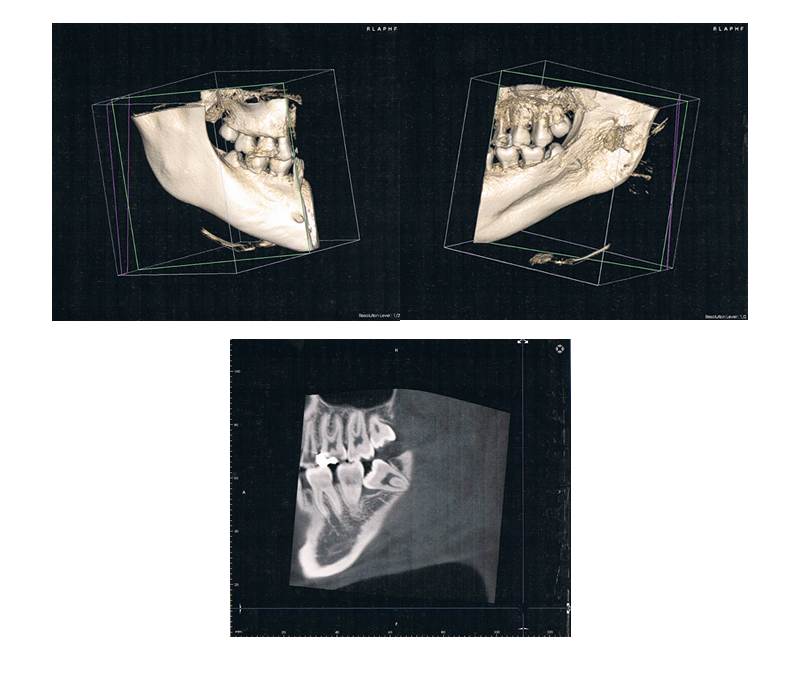

当院では歯科用のCTを導入いたしました。CTでは、従来のレントゲンでは見えなかった顎の骨の立体的な形態や、神経の位置把握、 さらに骨密度の診査にも利用できます。 立体画像で状態を確認できますので、患者様にとって安心、納得の治療が行うことが出来ます。